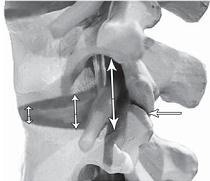

На фото № 6 макета позвоночника наблюдается смещение (подвывих) суставных поверхностей дугоотростчатых суставов. На фото № 7 наблюдается смещение (подвывих) суставных поверхностей дугоотростчатого сустава (увеличенный вариант). ![]() На фото № 8 макета позвоночника наблюдается перерастяжение дугоотростчатых суставов вследствие вытяжения. На фото № 9 наблюдается перерастяжение дугоотростчатого сустава (увеличенный вариант). ![]() Фото № 10 На фото № 10 макета позвоночника наблюдается нормальное взаимоотношение суставных поверхностей дугоотростчатых суставов, в норме высота межпозвонкового диска и межпозвонковых отверстий. ![]() Фото № 11 На фото № 11 макета позвоночника наблюдается смещение (подвывих) суставных поверхностей дугоотростчатых суставов. Подобное смещение, как правило, происходит вследствие развития дегенеративно-дистрофических процессов в межпозвонковом диске. При этом уменьшается высота диска, сужается просвет фораминального отверстия (межпозвонкового), что может способствовать ущемлению спинномозговых корешков (нервов) и сосудов. ![]() Фото № 12 На фото № 12 макета позвоночника наблюдается перерастяжение дугоотростчатого сустава вследствие вытяжения, расширение фораминального отверстия, а также растяжение задних отделов фиброзного кольца межпозвонкового диска и сближение вентральных (передних) отделов тел позвонков. Это приводит межпозвонковый диск в клиновидное состояние, что способствует выталкиванию содержимого межпозвонкового диска из передних его отделов в задние. |